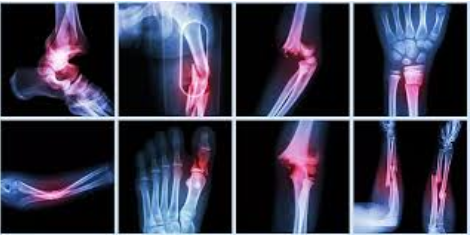

La traumatología y ortopedia se ocupan de las afecciones que afectan el sistema musculoesquelético, incluidas fracturas, luxaciones, enfermedades degenerativas como la osteoartritis, anomalías congénitas y lesiones traumáticas.

La traumatología y ortopedia es la especialidad de la medicina dirigida al estudio y tratamiento de los trastornos del sistema musculoesquelético: huesos, músculos y tendones, incluyendo lesiones traumáticas, como fracturas y luxaciones, enfermedades congénitas y del desarrollo, lesiones degenerativas (osteoartritis), entre otras.